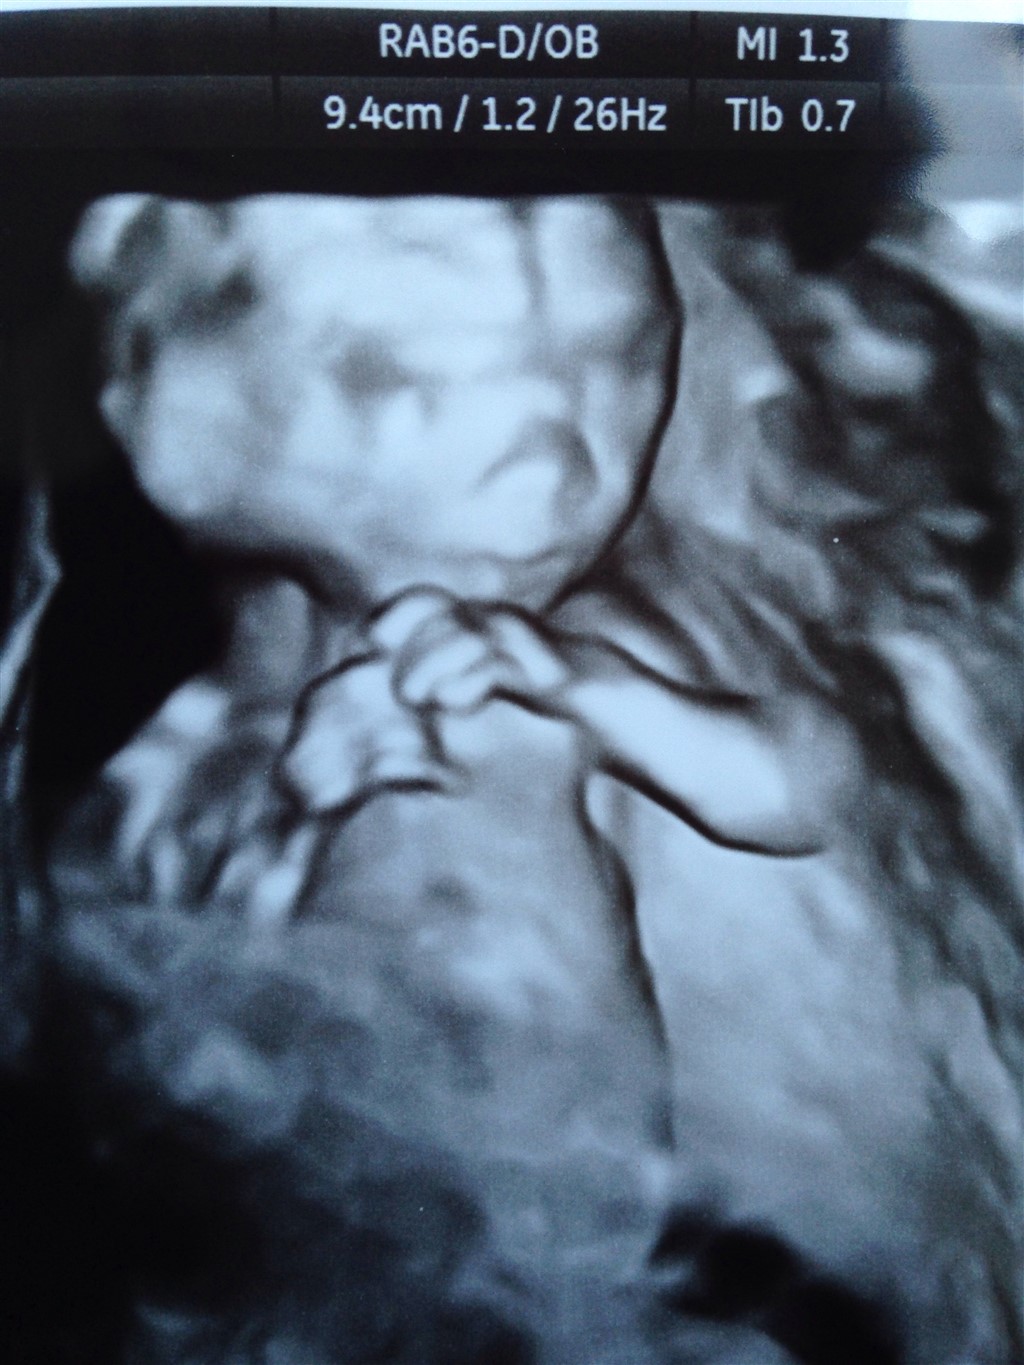

Hvordan går det med jer alle? Her går det fint. Jeg venter på md skanning om 4 uger. Jeg er begyndt at have lidt ondt i ryggen på jobbet, ellers mærker jeg ikke rigtigt noget til det udover maven bare vokser, men ser stadig bare tyk ud

jeg er 16+1 I dag og termin 15/10